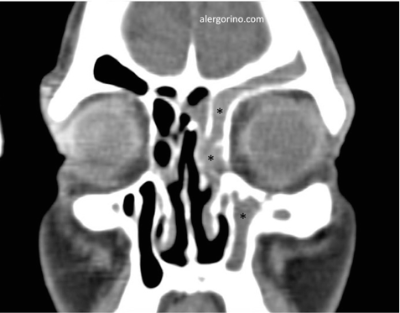

El diagnóstico se realiza mediante la historia clínica y una endoscopia nasal que proporcionan datos como la presencia de pólipos, la descarga mucopurulenta y el edema o la obstrucción de las áreas de drenaje de los senos paranasales. Si no se produjera una respuesta al tratamiento médico se evalua la situación de los senos paranasales mediante una tomografía computarizada (TC).

Los objetivos del tratamiento son: controlar la infección, reducir el edema del tejido, facilitar el drenaje, mantener la aireación de los senos paranasales, rompiendo el ciclo vicioso que conduce a la cronicidad. El tratamiento de la SC, con y sin póliposis, suele puede ser "en bocadillo": médico – quirúrgico – médico. Principalmente los lavados nasales en forma de duchas nasales, corticoides intranasales, antibióticos en caso de sobre-infección. La cirugía endoscópica está indicada cuando fracasa el tratamiento médico. En caso de la SC fúngica es imprescindible la apertura y limpieza adecuadas de los senos afectados.